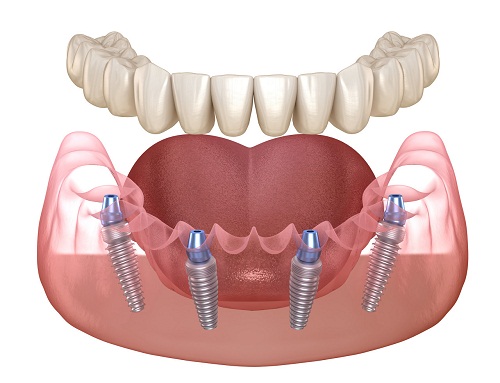

2. All-on-4/All-on-6即刻負重技術:快速,實現「一日得牙」(1-3天戴臨時牙)

這是革命性的技術,能極大縮短無牙期。它通過植入4-6顆特殊角度分布的種植體,來支撐整排牙橋。

核心優勢:手術當天或24-48小時內,就能安裝一付固定的臨時牙橋,患者可以立刻恢復基本的咀嚼和美觀。

後續階段:臨時牙橋需使用3-6個月,待骨骼完全愈合穩定後,再更換為精密的永久性牙橋。

總計耗時:獲得臨時固定牙僅需1-3天;獲得最終永久牙仍需等待約4-8個月。